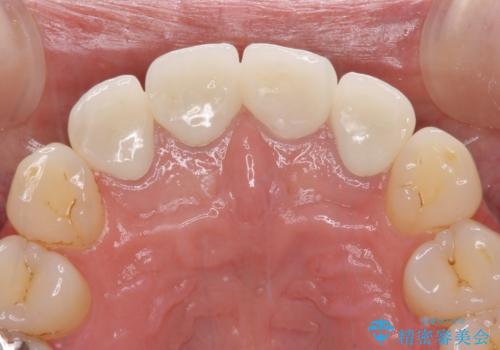

- 前歯のクラウンの変色や歯の変色を気にして来院された患者様です。

グラスファイバーを用いた土台により歯質を強化した上で、オールセラミッククラウンにて補綴することとしました。

統一感があり、歯肉ラインもきれいに整い、清潔感溢れる口元に仕上げることができました。